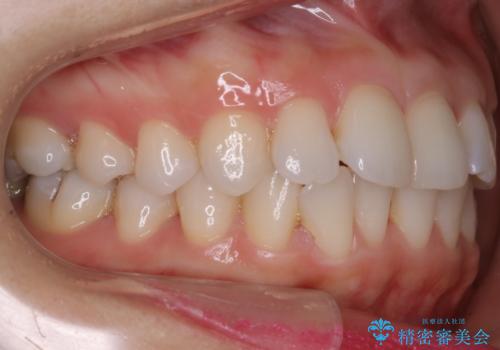

- 上下の前歯の細かいガタつきの治療をご希望されて来院されました。

奥歯部分にはガタつきや噛み合わせの問題などがほとんど見られず、前歯のガタつきも軽度だったため、インビザライン ライト パッケージでの部分矯正を行うこととなりました。

今回のケースでは奥歯の噛み合わせに問題がほぼみられなかったため、前歯の位置のみに焦点を当て部分矯正を行いました。

適応されるケースが限られるものの、適応であった場合の治療期間は全体矯正と比べると格段に短くなり、費用も抑えられます。